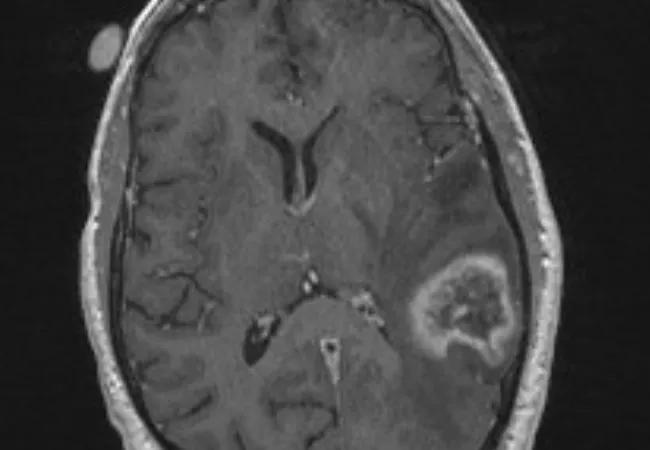

MRI of a patient with brain metastases